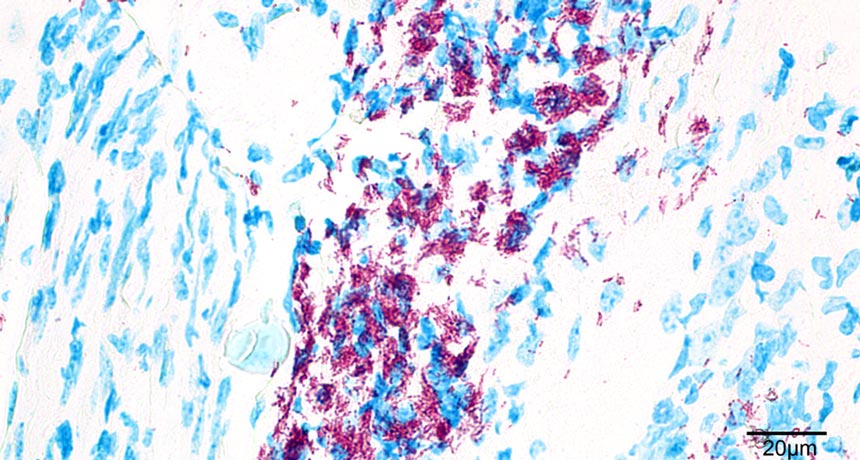

FOREST CHANGE Clearing forests and changing landscapes might affect how many people develop Buruli ulcer. The disease is caused by bacteria shown here (in red) in a section of otherwise healthy mouse tissue (in blue).

Angèle Bénard, Claudia Sala and Gerd Pluschke/PLOS ONE 2016